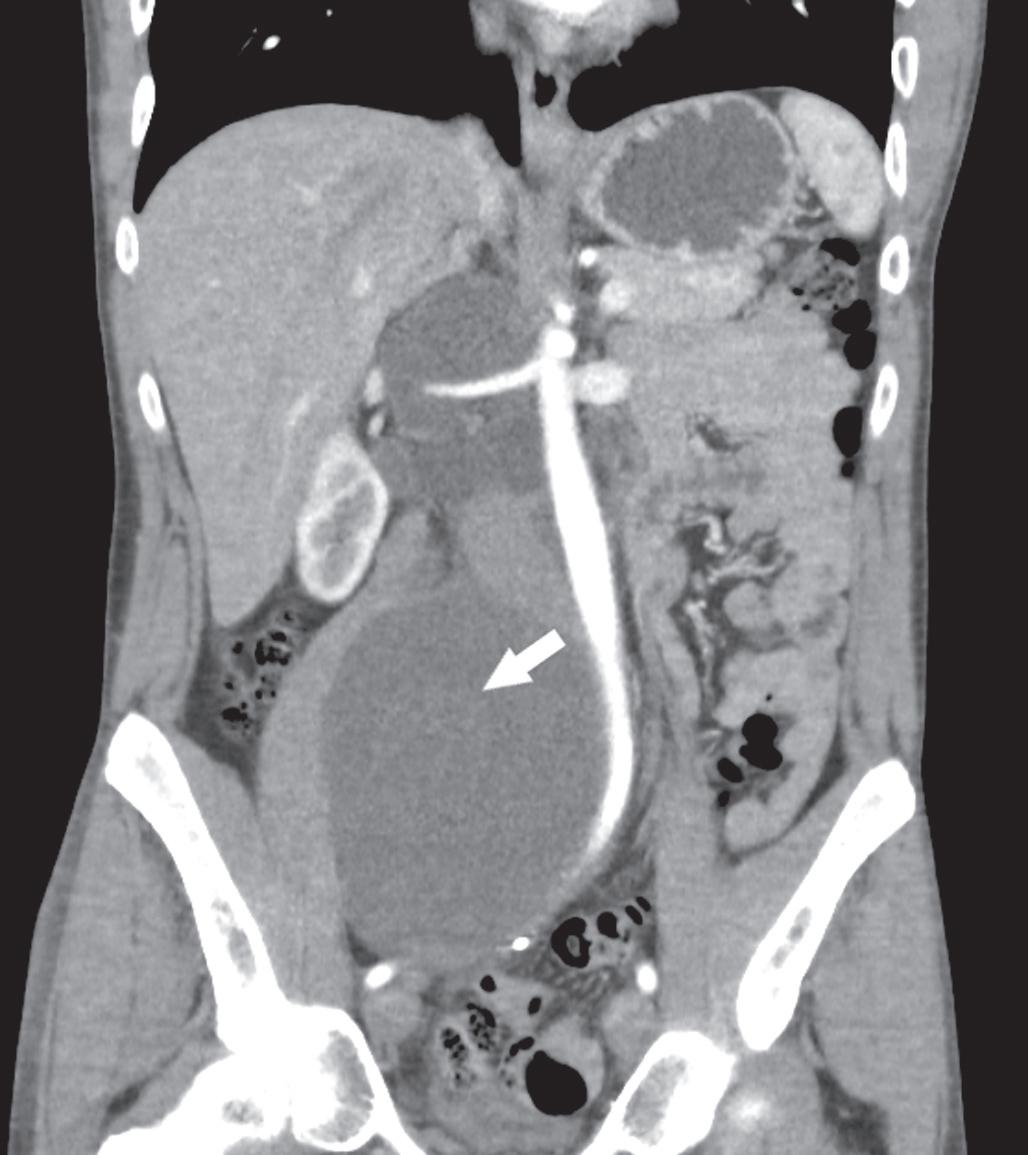

PH je jedn ou z nejčastějších a nejnáročnějších komplikací spojených s vytvořením stomie, vč. ileálního konduitu (obr. 1 a 2). Je definována jako protruze břišních orgánů skrze defekt v břišní stěně v bezprostřední blízkosti stomie [3]. Výskyt PH se u pacientů s ileálním konduitem pohybuje dle literatury v širokém rozmezí 10– 65 %, přičemž až 30 % z nich může vyžadovat chirurgickou intervenci kvůli bolestem, únikům moči, obtížím s lepením stomického sáčku nebo zánětům a podráždění kůže [4,5].

Obr. 1. Pacient s parastomální hernií po otevřené radikální cystektomii s použitím ileálního konduitu.

Fig. 1. Patient with parastomal hernia following open radical cystectomy with ileal conduit.

Obr. 2. Nález na počítačové tomografii u pacienta s parastomální hernií po otevřené radikální cystektomii s použitím ileálního konduitu.

Fig. 2. Computed tomography finding in a patient with parastomal hernia following open radical cystectomy with ileal conduit.